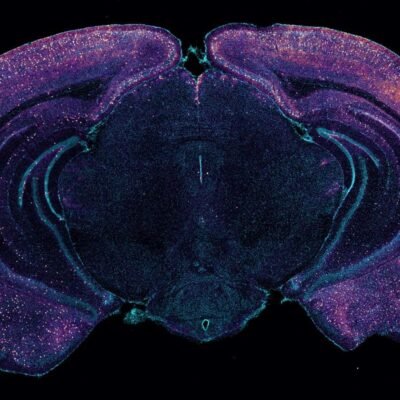

[ad_1] A cross-section of a mouse’s brain highlighting neurons that seem to release a molecule that increases toxin clearance Tsai Laboratory/MIT Picower Institute A new